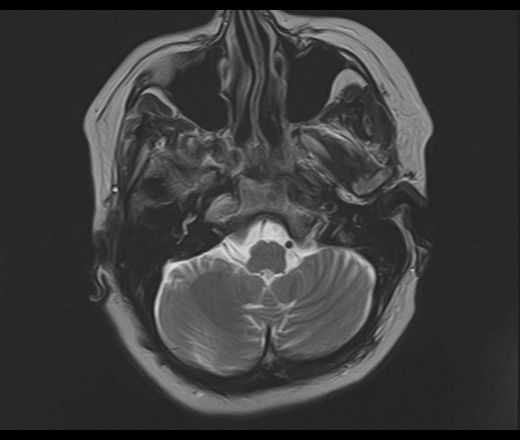

У пациентки 1960 г.р. с 2005 наблюдается птоз, диагноз миастении исключен. МРТ ГМ впервые выполнено в августе 2015 г в плановом порядке, новых жалоб не было, по описанию МРТ - очаговые изменения белого и серого вещества больших полушарий и ствола мозга - признаки энцефаломиелита.

В сентябре 2015 новое МРТ: субкортикальные очаги в белом веществе больших полушарий, не накапливающие контраст; уменьшение размеров ряда очагов - Данных за демиелинизирующее заболевание нет, поствоспалительные изменения. Консультирована в НИИ неврологии, предположено демиелинизирующее заболевание вторичного генеза. В неврологическом статусе: правосторонний птоз, ограничение конвергенции, асимметрия носогубных складок.

Сейчас вновь сделано МРТ, появлись 2 новых очага: в полюсе правой височной доли и поперечной височной извилине слева. Очаг в задних отделах левой теменной доли (угловая извилина) увеличился в размерах. С контрастом пока не работаем.

Подскажите, пожалуйста, что это за процесс? Поражено только белое вещество или серое также? Есть ли поражение ствола мозга?

Действительно, динамика отрицательная и на первичную демиелинизацию не тянет. Какой-то продолжающийся энцефалит, какой именно и гадать нечего, это не наше дело, навскидку можно написать длинный ряд типа Эбштейна-Барра и пр, всё требует серологического доказательства.. В стволе ничего не увидел. Поражено белое и серое вещество.